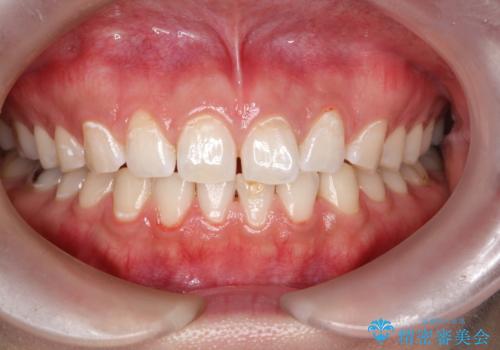

- 半年ぶりの来院で、全体的なチェックとクリーニング希望でした。PMTC(自費クリーニング)60分コースを行いました。

PMTCとは、プロフェッショナル(歯科衛生士)メカニカル(機械的)トゥース(歯)クリーニング(清掃)の略です。歯科医院にて、いろいろな機械・材料を使用し汚れを落とします。

磨き残しや、細菌は歯の表面がザラザラしている部分につきやすいです。そのためPMTCを定期的に繰り返すことで、歯の表面がツルツルの状態である期間が長くなるため、虫歯や歯周病予防につながります。